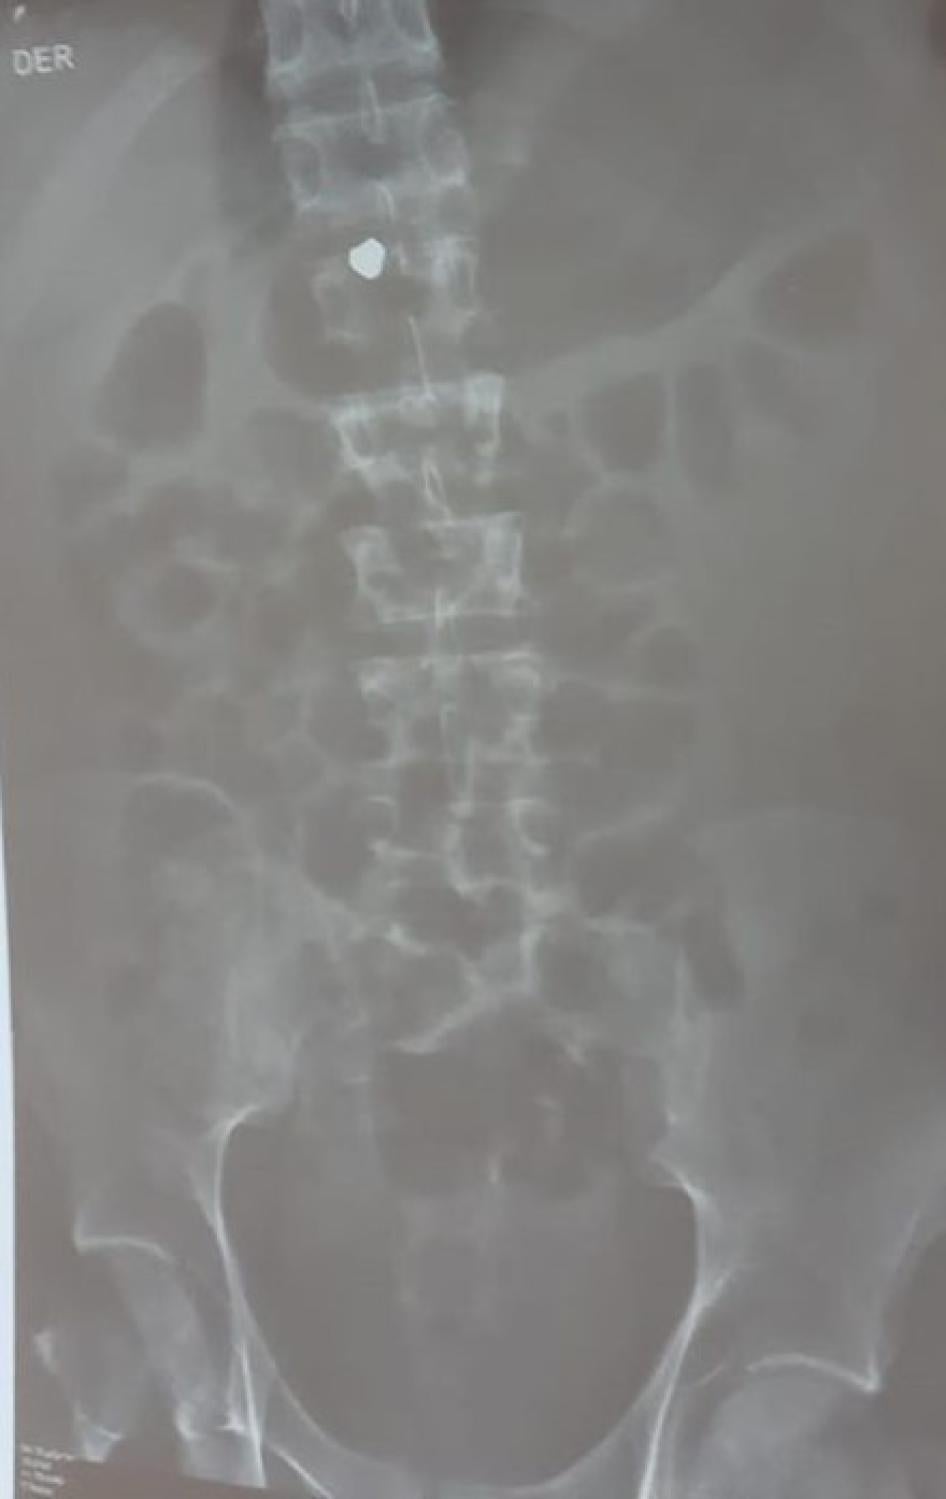

X-ray showing a marble lodged in Luis Aguilar Rodriguez’s lung. Photo courtesy of Luis Aguilar Rodriguez’s family.

X-ray showing a pellet, believed to be lead, lodged in Jon Cordero’s spinal cord. Photograph courtesy of Jon Cordero’s family.